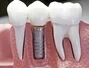

Dental implants are used for replacing missing teeth. Implants are more durable and longer lasting than bridges or partial dentures because they replace both the tooth and the root. A dental implant consists of the implant that is inserted in the jawbone, an abutment, and a porcelain crown.

Benefits

• Implants restore proper chewing function and so you can enjoy foods previously too "difficult" to eat.

• You regain the closest thing to the look, feel and function of your natural teeth

• You can clean and floss normally

• No fear of caries & sensitivity of teeth No more irritated and painful gums

• Prevent the shrinking of bone and gums

• You feel confident that your replacement teeth won’t move or loosen when eating or speaking

• Last the longest of all the options available for replacing teeth

• Cutting of natural teeth is avoided